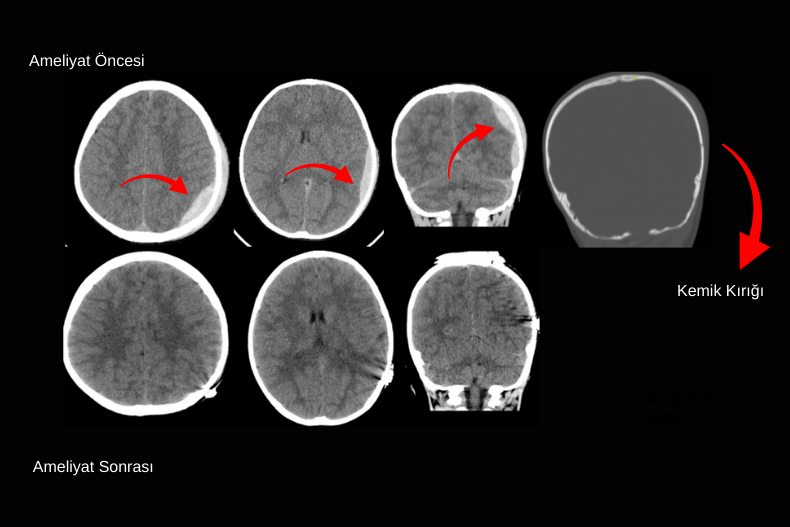

Dekompresif kraniektomi genellikle BT’de belirgin orta hat kayması (shift), bazal sisternlerde silinme ve ciddi beyin ödemine bağlı kitle etkisi görülen hastalarda uygulanır. Bu bulgular, artmış kafa içi basıncının beyin dokusunu karşı tarafa ittiğini ve beyin sapı basısı riskinin oluştuğunu gösterir. Cerrahi sırasında kafatasının bir bölümü çıkarılarak beyne genişleme alanı sağlanır ve bu sayede bası azaltılır, serebral perfüzyon korunur.

Özellikle masif akut subdural hematom olgularında hematom boşaltıldıktan sonra beyin dokusunda ciddi ödem gelişmişse kemik flep hemen yerine konulamayabilir. Bu durumda kemik geçici olarak çıkarılır ve hasta stabilize edildikten haftalar ya da aylar sonra kranioplasti ile tekrar yerine yerleştirilir. Amaç, erken dönemde beyin şişmesine karşı yeterli alan tanıyarak sekonder hasarı önlemektir.